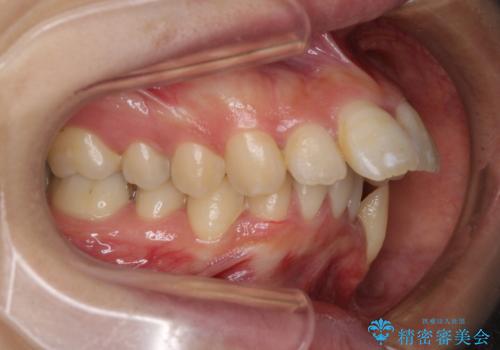

- 口元がひどく突出するくらいの上顎前突を気にして来院された患者様です。

舌の突出癖が顕著で、上顎歯列は完全なV字型となっている状態でした。

下顎歯列にも八重歯があり、上下左右の第一小臼歯4本を抜歯して、ワイヤー装置にて矯正治療を行うこととしました。